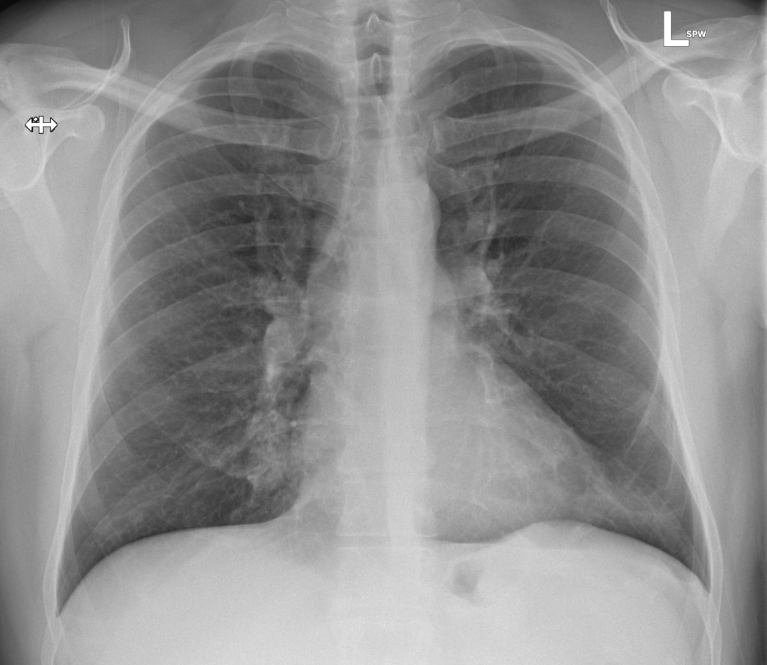

His CXR and ECG are shown below, what do you think?

• Lung fields are largely clear, there is no pneumothorax, pulmonary oedema, or cardiomegaly visible.

• Patchy pacifications at the right mid-zone (with loss of right heart border) and left lower zones raise possibility of infection. They could also however represent e.g. pulmonary infarction.